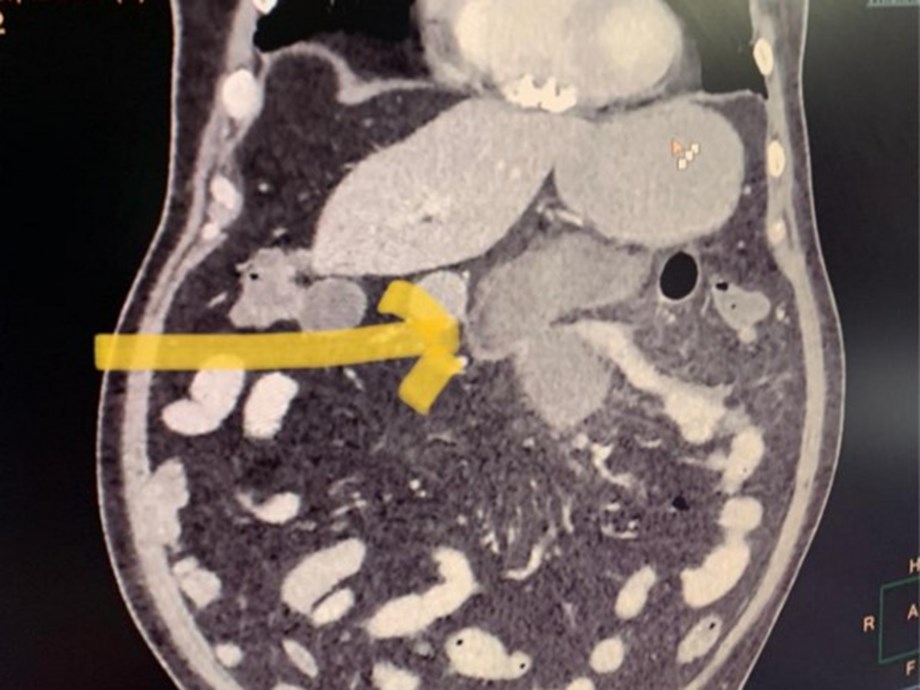

Hence then, the article about delhi hospital reports black fungus of small intestine was published today ( ) and is available on Devdiscourse ( Middle East ) The editorial team at PressBee has edited and verified it, and it may have been modified, fully republished, or quoted. You can read and follow the updates of this news or article from its original source.